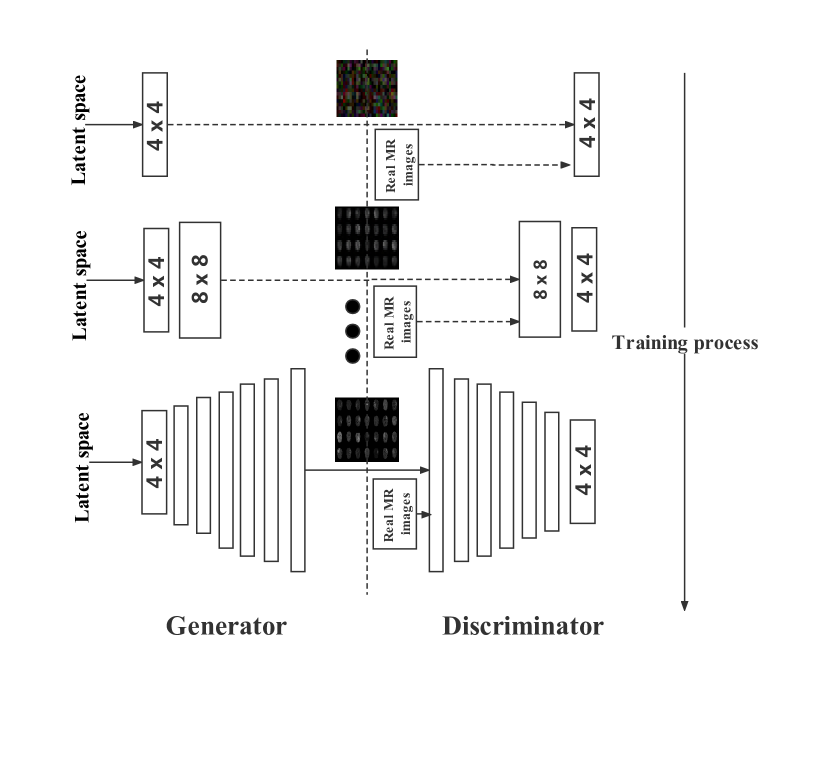

Han et al. [12] exploited PGGAN architecture to synthesize original-sized 256 x 256 realistic brain MR images, improving the accuracy of tumor detection. PGGAN proposed by Karras et al. [30] is firstly able to generate 1024 x 1024 realistic images as it uses a novel training strategy with a progressively growing generator and discriminator: starting from low resolution, newly added layers capture fine-grained details as training progresses. As Figure 3 shows, they successfully adopt PGGAN to generate realistic 256 x 256 brain MR images.

PGGAN There are mainly three improvements that enable PGGAN to generate high-quality 1024 x 1024 high-resolution images:

Progressive Growing Training Strategy: During training, new blocks of convolutional layers are systematically added to both the generator model and the discriminator models [30]. The incremental addition of the layers allows the models to learn coarse-level detail effectively and later learn ever finer detail, both on the generator and discriminator side. Attentionally, When new layers are added to the networks, PGGAN fades current layers in smoothly. That avoids sudden shocks to the already well-trained, smaller-resolution layers. Further, all layers remain trainable during the training process, including existing layers when new layers are added.

Increasing Variation Using Minibatch Standard Deviation: The minibatch layer in discriminator measures the diversity within a minibath, which enable generator to escape mode collapse [30].

Equalized Learning Rate and Pixelwise Feature Vector Normalization [30]

PGGAN utilizes WGAN-GP loss function as follows:

Where represents the sample distribution randomly along with the space between the data distribution and the generator distribution [7].

PGGAN-SSIM There are no differences between PGGAN-SSIM and original PGGAN architectures. However, due to the small-scale training dataset and the size limitation of the minibatch layer in the discriminator, mode collapse possibly happens in the training process. Therefore, we add the SSIM loss function to the generator, forcing it to synthesize images with more diversity. The total loss is as follows: